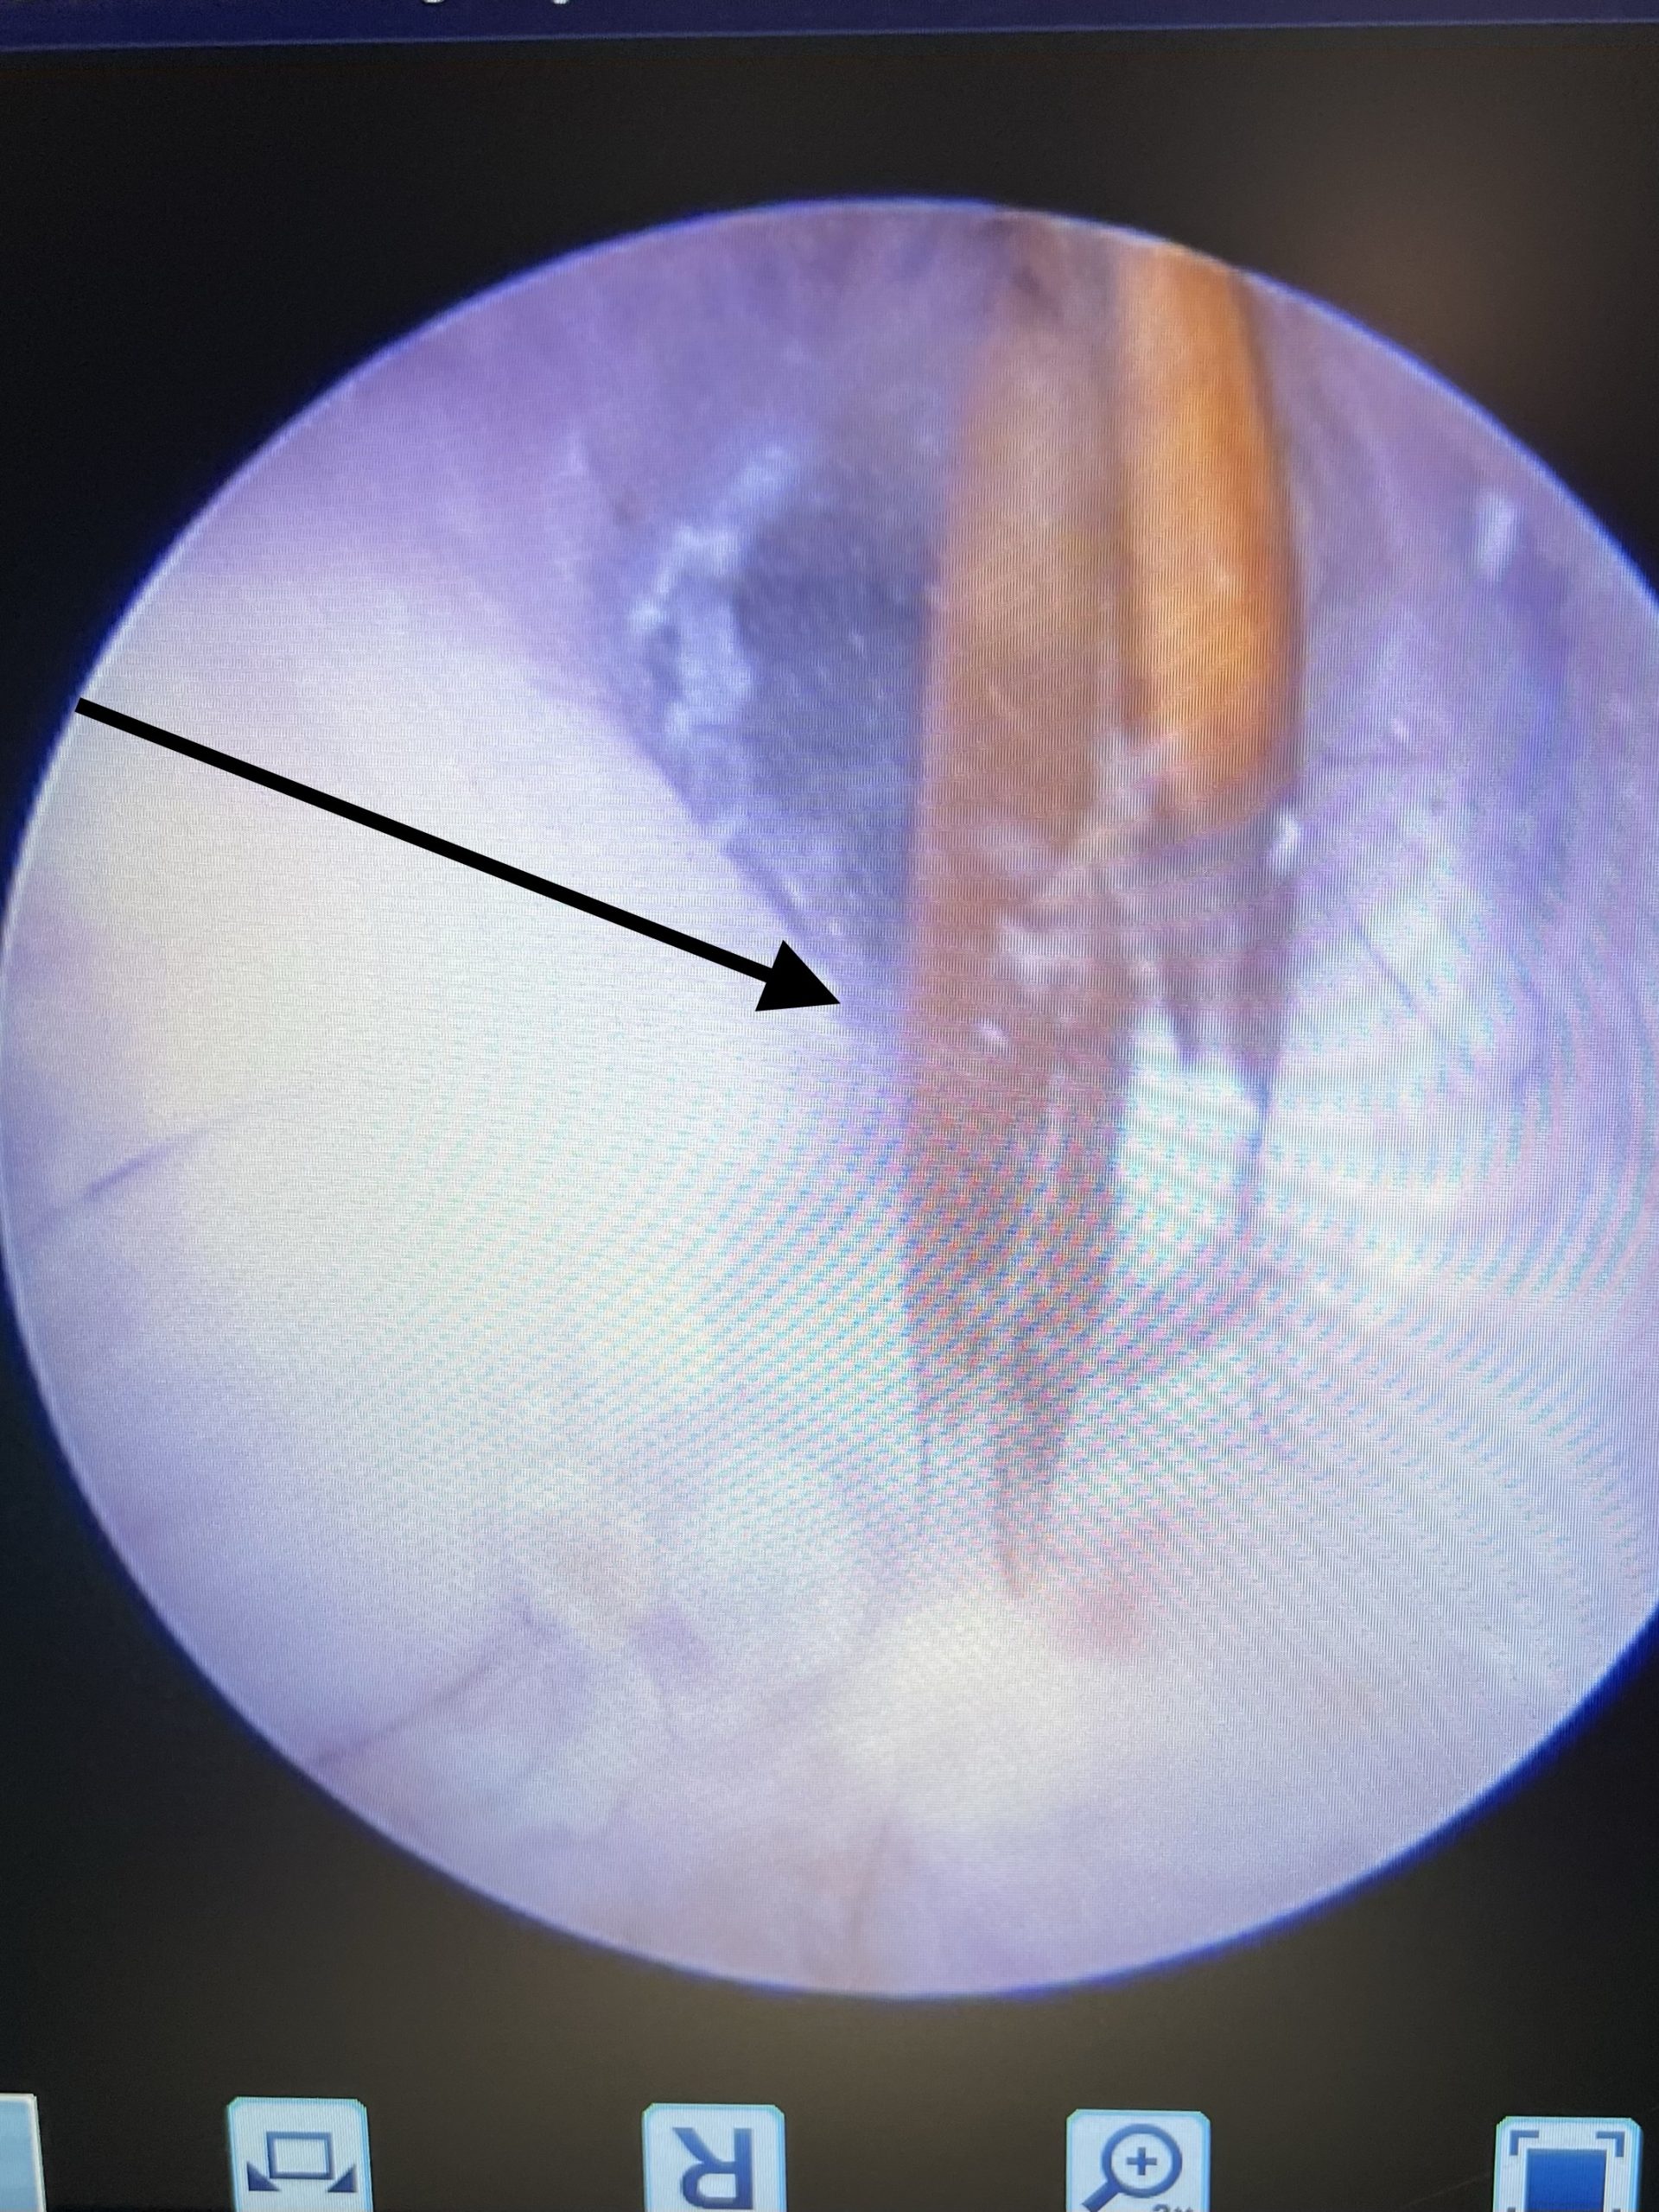

Pseudomonas är en bakterie som kan ge allvarlig infektion av hörselgången med sår och smärta som följd. Ofta leder infektionen till att trumhinnan spricker och att hunden får mellanöroninfektion. Pseudomonas kan inte infektera ett friskt öra utan drabbar hundar med upprepade öronbesvär exvis vid allergier, men när det väl blivit en infektion måste den behandlas. Bakterien är av naturen resistent vilket gör den svårbehandlad men vad som ytterligare gör den svårbehandlad är att den bildar så kallad biofilm. Biofilm ses som slemmigt sekret i hörselgången och gör att bakterien kapslar in och skyddas så antibiotika inte kan nå in. För att kunna bli av med Pseudomonas behöver man tvätta och skölja örat med speciella rengöringar som löser upp biofilmen. Oftast krävs det narkos och spolning med videootoskop för att det ska bli helt rent och för att kunna undersöka hörselgången. Detta görs för att hunden har så ont, men även för att det först efter rengöringen gör att man med videootoskopet kan se om trumhinnan är skadad och infektionen gått in till mellanörat.

Öronspolning med videoendoskop är en specialutrustning där man med en videokamera kan se hela hörselgången, trumhinnan och in i mellanörat. Under spolningen ser man allt man gör på en videoskärm och kan effektivt spola rent hörselgången ned till trumhinnan. Det ger även möjlighet att punktera trumhinnan för att kunna provta och spola mellanörat om det behövs. Man kan även lättare operera ut tumörer eller ta biopsier på vävnadsförändringar via denna teknik.

Öronspolning hos oss görs med så kallad videootoskopering, vilket är ett endoskop med videokamera som ansluten till en spolmaskin. Med denna utrustning ser man precis vad man gör och kan exempelvis punktera trumhinna och spola ur mellanörat. Djuret sövs och tubas i narkos för att inte få sekret och spolvätska i lungorna.